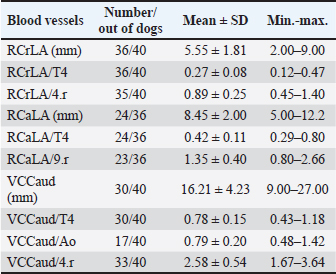

Fig. 1. A and B. Measurements of LA and SA in LL (A) and DV (B) views, with marked T4, S4, M, TI length: LA – long axis, SA – short axis, T4 - the length (mm) of the body and caudal disc of the T4vertebra, S4 - the length (mm) of the S4, M – the length (mm) of the M, TI - the length (mm) of a dog’s TI. Modified vertebral heart sizeThe cardiac LA and SA in LL view were measured as previously described, added up, and then transformed from mm into whole and 0.01 of VHS units (v), by dividing the sum of both axes by the length (mm) of the body and caudal disc of the T4 (VHS-LL) (Spasojević Kosić et al., 2007). The same was done to calculate the cardiac VHS in DV radiographs (VHS-DV). Manubrium heart scoreThe sum of the measured cardiac LA and SA (in mm) was normalized by the corresponding M length (mm) according to the method described by Mostafa and Berry (2017). The same was done for both MHS in LL and in DV radiographs (MHS-LL and MHS-DV). Sternebral heart sizeTo determine SHS, the length of the S4 is used as a unit of measurement. The sum of the measured LA and SA in mm was divided by the length of the S4, both for LL and DV radiographs, in order to get SHS in LL and DV (SHS-LL and SHS-DV). Thoracic inlet heart sizeThe sum of LA and SA (mm) was divided by the length of a dog’s TI. The shortest TI was measured from the craniodorsal M to the cranioventral first thoracic vertebra as described by Marbella Fernández et al. (2023a). For this method, cardiac silhouette measurement was performed only in LL radiographs (TIHS-LL). Cardiac sphericity indexCSI was calculated by dividing the cardiac SA by LA obtained from LL and DV radiographs (CSI-LL and CSI-DV) (Guglielmini et al., 2012). Measurement of blood vesselsObjective methods for assessment of blood vessels relevant to the HWD included several measurements (Fig. 2A and B) and calculations. The diameters of blood vessels relevant for the HWD (RCrLA, RCaLA, and VCC) were first measured and expressed in absolute values (mm). The diameters of the vessels were measured perpendicular to their LA. Relative measurements of the relevant blood vessels were expressed as ratios to the T4 (for all three blood vessels), and to the 4.r (for the RCrLA and VCC), to the 9.r (for the RCaLA), and to the Ao (for the VCC). The T4 was measured as described in modified VHS methods. The measurement of the 4.r was done on its proximal part as the smallest diameter. The measurement of the 9.r was measured at its intersection with the RCaLA. The Ao was measured at the descending part (Herrtage and Denis, 1997; Lehmkuhl et al., 1997; Arya et al., 2021).

Measured values of the T4, the M and the S4 varied among the dogs, but significant correlations were determined among them. The strongest correlation existed between the T4 and the S4 (r=0.91, p < 0.05; 0.95CI; R2 =0.83), but the correlation between the T4 and the M (r=0.86, p < 0.05; 0.95CI; R2 =0.74), and the M and the S4 were also significant (r=0.84, p < 0.05; 0.95CI; R2 =0.70). However, the correlations between the T4, the M, the S4, and the length of TI have not been found. Significant correlations (p < 0.05) between LA, SA, the sum of LA and SA, and each skeletal unit (T4, S4, M, TI) were detected both in LL and DV radiographs. The strongest correlations were found between LA, SA, the sum of LA and SA, and T4 (very strong and strong, p < 0.05) and S4 (very strong and strong, p < 0.05). There were strong correlations between LA, SA, the sum of LA and SA, and TI (r > 0.7, p < 0.05). Moderate correlations existed between LA, SA, the sum of LA and SA, and M (r > 0.6, p < 0.05). Blood vessel (RCrLA, RCaLA, and VCC) measurements, as absolute and relative values, are shown in Table 5. The RCrLA could be measured in the majority of dogs (36 out of 40). In four dogs, this vessel could not be assessed because of areas of increased densities in the cranial lung lobes and perivascular opacities. The RCaLA could not be defined in 12 dogs, due to perivascular opacities, increased densities in lung lobes, incorrect positioning, or the dog’s respiratory phase. It was not possible to assess the VCC in 10 dogs. The reasons for this were: respiratory phase, perivascular opacities, increased opacity in that area of the lung field, superposition with ribs or bronchi. Table 5. The measurements of the relevant blood vessels in the dogs with HWD.